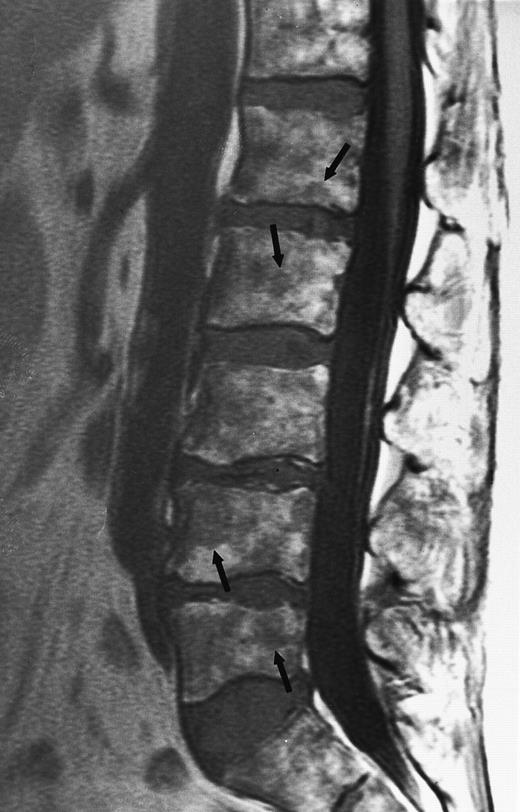

On T1-weighted MR images, lymphomatous involvement of the bone marrow is seen as diffuse, primarily heterogeneous replacement of the marrow and less frequently as focal marrow lesions (Figs 11 and 12).43,46 47 On T2-weighted images, the signal of the abnormal marrow increases, and on T1-weighted images after the intravenous administration of contrast, the abnormal marrow enhances. The MR patterns of lymphomatous involvement of the bone marrow may be indistinguishable from similar patterns in myeloma, leukemia, and other malignant or benign diseases of the bone marrow. MR imaging cannot differentiate between the different histologic subtypes of lymphoma.

An 8-year-old boy with Burkitt's lymphoma and diffuse marrow involvement. Fat-suppressed, T2-weighted fast spin echo (3000/96, TR/TE) sagittal MR image of the lumbar spine shows heterogeneous signal intensity of the bone marrow and epidural extension of tumor (arrowheads) at the level of L5 and L2, with apparent preservation of the vertebral cortex.